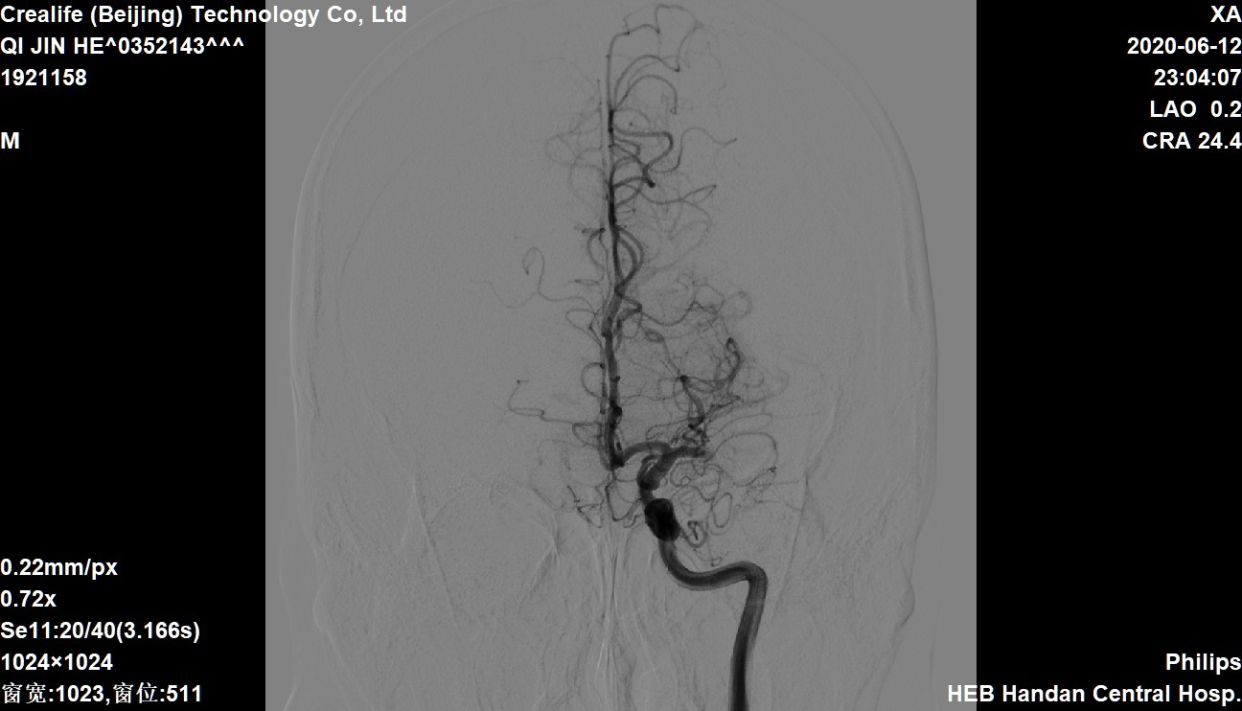

navi到位

微导管到位造影,首过效应阴性

首过效应阴性

支架释放

释放支架后造影,提示有下干充盈缺损